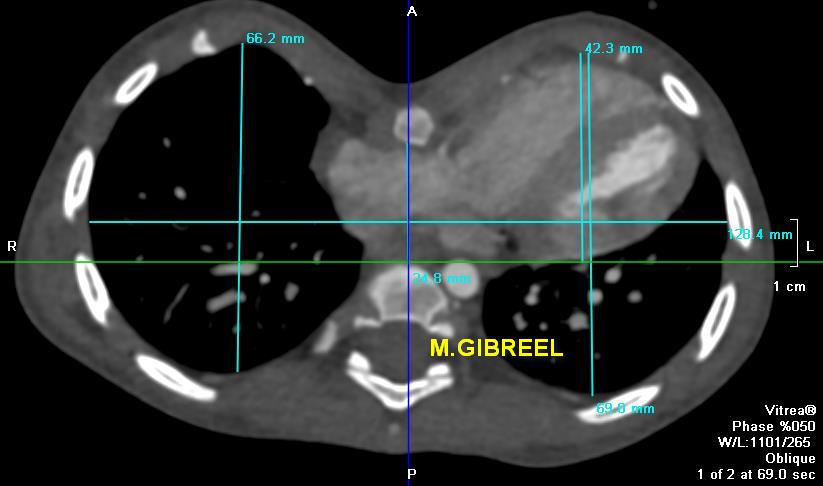

Pectus excavatum (Grade1), with longitudinal deformation of the RV & chest asymmetry,,, important measurements

MGibreel1's tweet image. Pectus excavatum (Grade1), with longitudinal deformation of the RV & chest asymmetry,,, important measurements